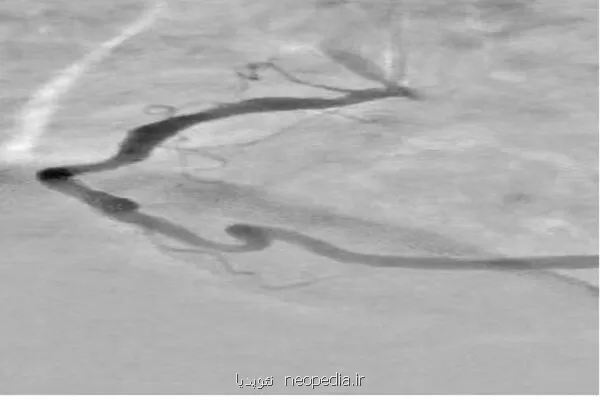

آخوندی ضمن اشاره به علل انتخاب این مطالعه، توضیح داد: در آنژیوگرافی قلب، تداخل سایه های ناشی از بافت ها و استخوان های قفسه سینه و همین طور حرکات تنفسی و ضربان قلب سبب می شود تشخیص دقیق عروق کرونری دشوار شود. این مسئله منجر به نیاز به تزریق بیشتر ماده حاجب و دریافت دوز بالاتر اشعه توسط بیمار می شود.

وی اضافه کرد: ازاین رو هدف این پژوهش حل این مشکل و عرضه روشی دقیق تر و ایمن تر برای بهبود کیفیت تشخیص گرفتگی ها توسط پزشک متخصص بوده است.

آخوندی خاصیت های این طرح را شامل افزایش وضوح عروق کرونری در تصاویر آنژیوگرافی، کاهش نیاز به تزریق مقدار زیاد ماده حاجب و درنتیجه کاهش خطرات در رابطه با آن برای بیمار دانست و اضافه کرد: همین طور نسبت به شیوه های سنتی، زمان پردازش تصاویر را بطور قابل توجهی می کاهد و می تواند حتی با در اختیار داشتن یک تصویر تکی حاوی ماده حاجب هم عمل اصلاح و پردازش را انجام دهد. سرانجام، سودجستن از فناوری شبکه های عصبی عمیق، امکان استخراج و بازسازی هوشمند پس زمینه و جداسازی بهتر عروق را فراهم می آورد و طرح را از نظر علمی و کاربردی در سطح شیوه های نوین پردازش تصویر پزشکی قرار می دهد.